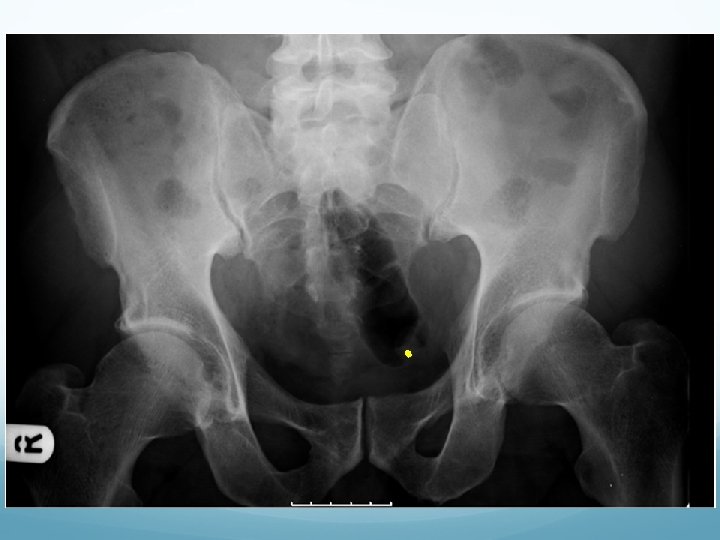

What to look for on a KUB � 90% stones are radio-opaque � Ureteric stones are sausage shaped due to peristalsis of ureters 1. Outline of kidneys 2. Path of ureters � Hila of kidneys L 1 � Tips of transverse processes � SIJ at pelvis 3. Sites of impaction � PUJ � Pelvic Brim � VUJ 4. Rest of abdominal film

1. Outline of kidneys 1. Path of ureters 1. Sites of impaction 1. Rest of abdominal film

What to look for on an IVU � ALWAYS look at KUB first � CT KUB is gold standard, and only option if U+Es are abnormal 1. Nephrogram � � Contrast in kidney Persistent increasingly dense nephrogram in obstruction 2. Pyelogram � Calyces: � � � ? clubbed / more prominent Extravasation of contrast Ureters: � � � Peristalsis: Normal Dilatation Standing column